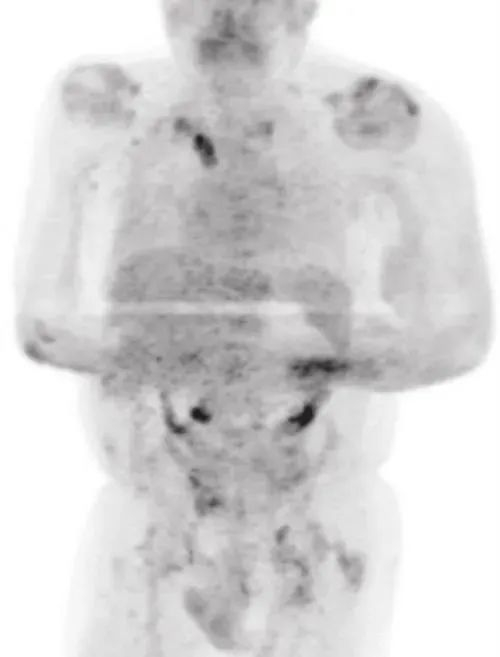

2020年年中,男子的身体突然之间暴瘦,并且全身淋巴结肿大,他赶紧到医院检查,结果确诊罹患经典型霍奇淋巴瘤,PET-CT扫描提示疾病分期为3期。

也就是说,男子此时是一名癌症晚期患者。CT照片也显示,癌细胞扩散到了他身体的各个地方。

四个月后,男子回医院复查。PET-CT扫描却提示,他体内的大部分肿瘤竟然神奇地都消失了。更为夸张的是,与肿瘤有关的生物指标直接下降了约9成。